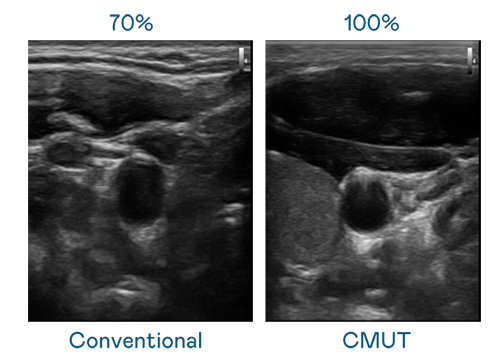

CMUT 技术是一种用电容式微机电元件来产生超音波讯号的技术。与传统 PZT 压电式技术相比,CMUT 频宽增加 30%,更宽频的超音波讯号让影像解析度大幅提升,是实现高影像品质医疗超音波扫描、促进精准医疗发展的关键技术。

超音波影像的解析度高低,首先取决于探头能发出的讯号频宽。东升国际链接入口 CMUT 可提供高清晰的超音波讯号,提供高频宽、高灵敏度、影像纹理细节更高的超音波影像,协助医护人员缩短影像判读时间及利用精准的医疗影像进行诊断。